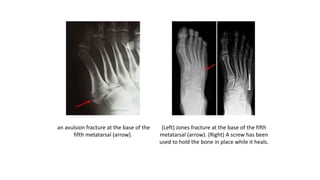

• A stress fracture can also come from a

sudden increase in physical activity or a

change in your exercise routine.

(Left) The four parts of each metatarsal.

(Right) fracture in the shaft of the 2nd

metatarsal.